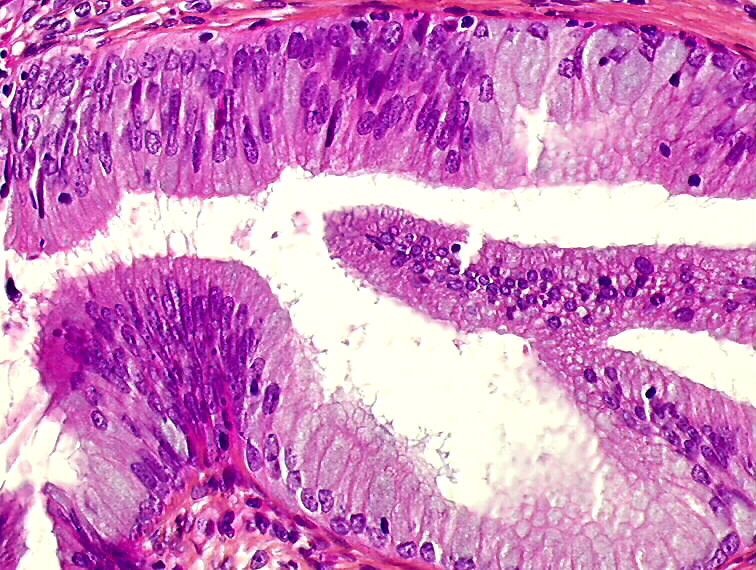

Low grade dysplasia ofglandular epithelium. Compare with normal What Is Glandular Dysplasia Hsil indicates squamous cells that appear very abnormal and signify the possibility of a precancer or cancer of the cervix. The purpose of this commentary is to summarize the current published data that forms the basis for the recent delineation of endometrial. In this article, the authors briefly review the historical evolution of the various putative precursor lesions for type. What Is Glandular Dysplasia.